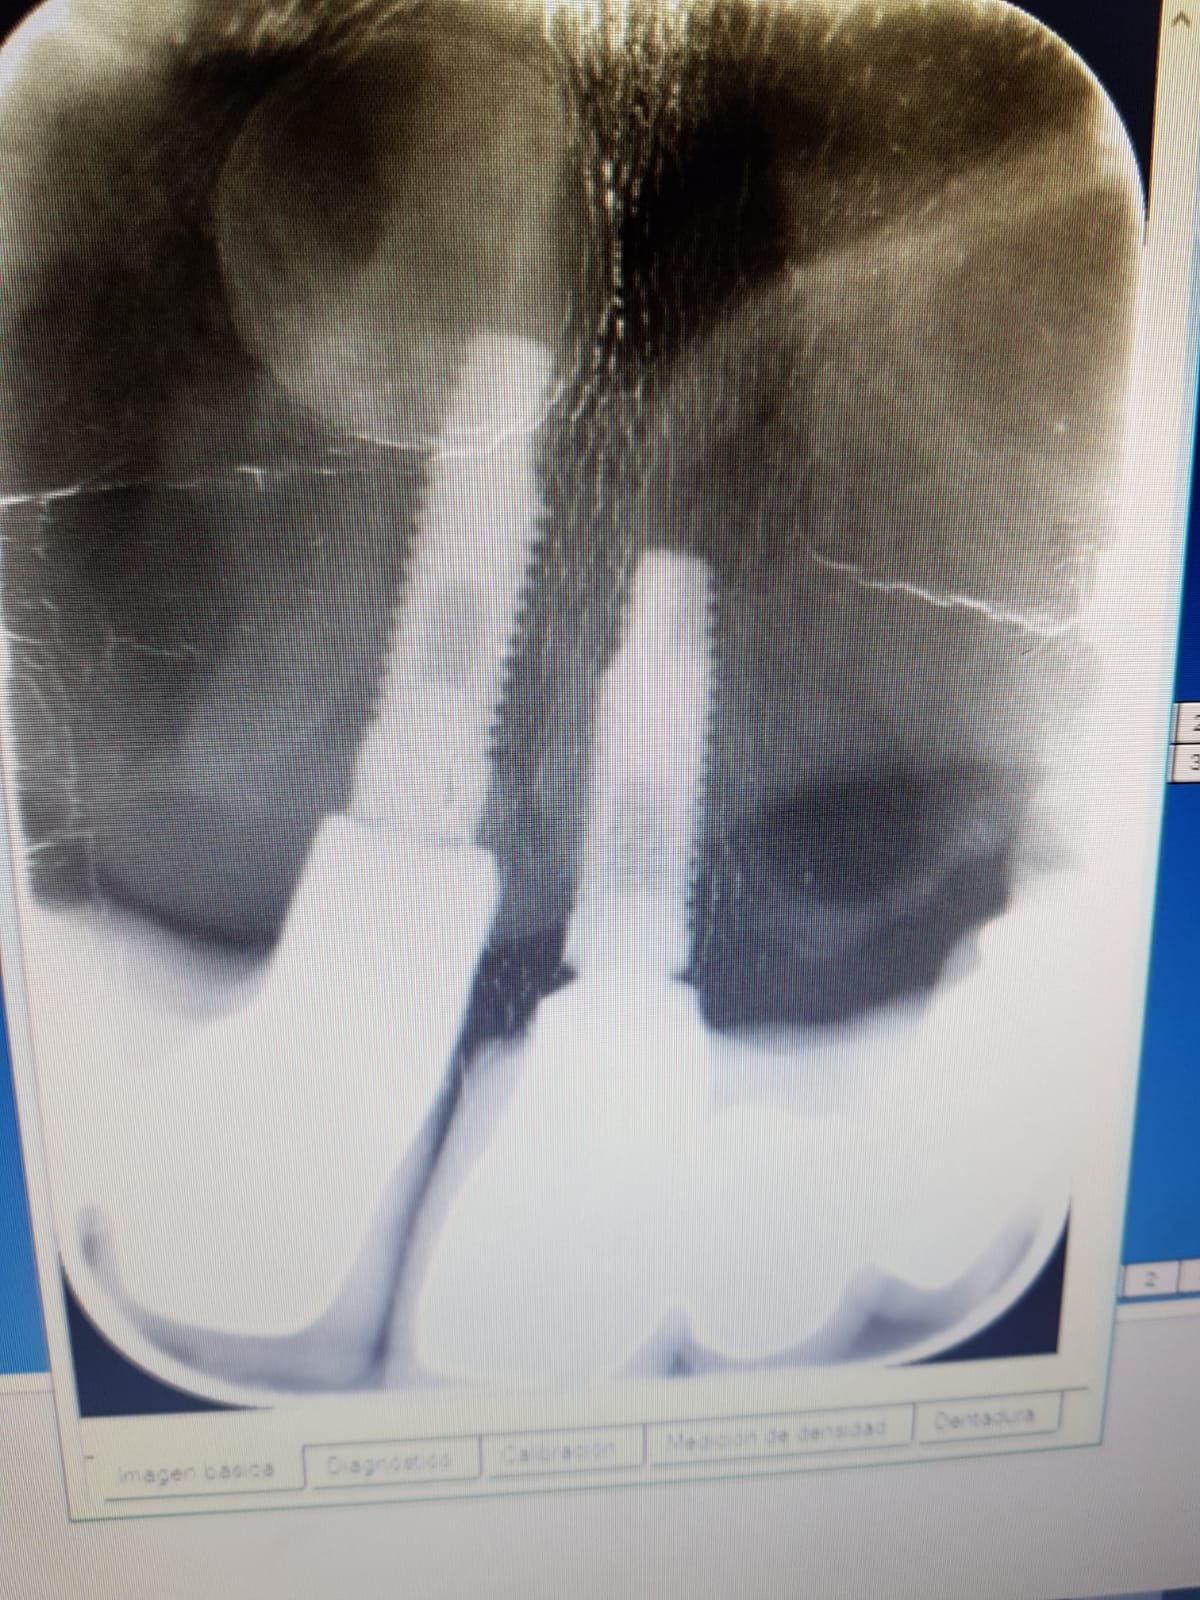

Buenos días. El otro día llegó a la consulta una paciente con implantes uno de ellos con movilidad de la corona. Se consiguió descementar pero no sabemos con qué apretar el [...]